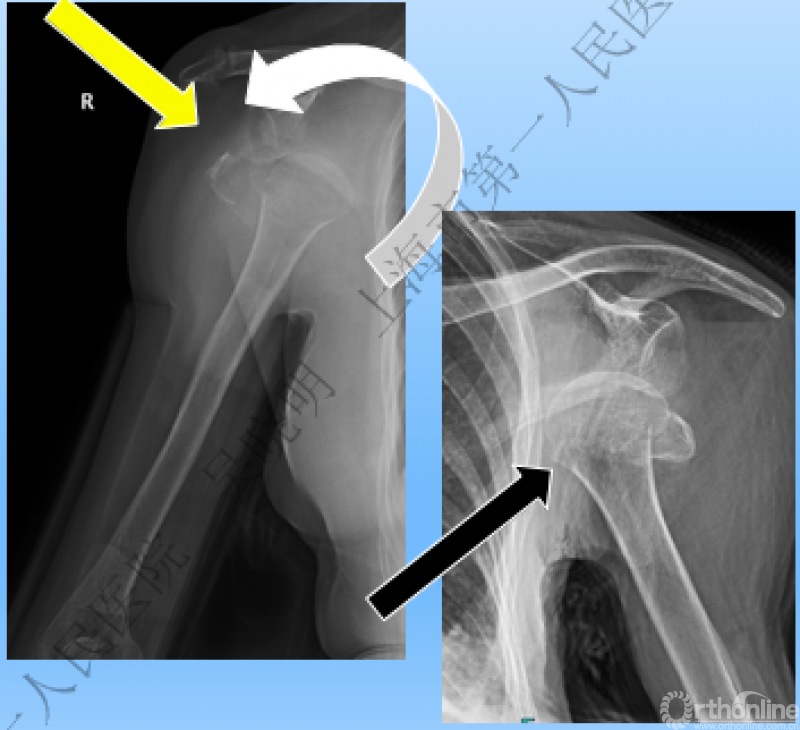

特别警惕伴肱骨头外翻合并大结节骨折的肩关节脱位

警惕:有无肱骨头外翻

肩关节前脱位伴大结节骨折:颈干角正常

无肱骨头外翻伴大结节骨折的老年性肩关节前脱位

Neer 分型:二部分大结节骨折脱位:手法复位

伴大结节骨折的老年性肩关节前脱位伴肱骨头外翻

肩关节前脱位合并大结节骨折&肱骨头外翻:外翻压缩型(Neer 分型)

对这型骨折进行手法复位会导致肱骨头和肱骨干之间的连续性消失。肱骨头和肱骨干之间连续性尚存,肱骨头前脱位(Robsion 3b)